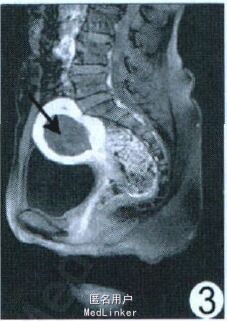

查体:子宫增大如孕8 周。实验室检查:血绒毛膜促性腺激素1.76 mIU/ml 。超声:子宫实性占位, 肌瘤变性。M RI :子宫明显不均匀增大, 宫腔内见约5.13 cm ×4.62 cm 类圆形异常信号, T1WI 呈等低信号, 其内见部分高信号(图1), T2WI 呈低信号, 其内夹杂线状、片状明显高信号(图2);增强后无强化(图3)。M RI 诊断为子宫腔内占位:子宫肌瘤(黏膜下型), 大部分变性。

稽留流产MRI 示子宫内膜明显增厚, T1WI 为等低信号, T2WI 呈低信号, 其内可夹杂高信号, 增强后病灶中央有或无强化。而黏膜下子宫肌瘤变性, 增强扫描中后者病灶周围有强化, 可资鉴别。DOI:1003-3289(2011)09-1912-01